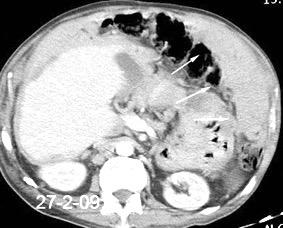

Absceso secundario a perforación de carcinoma. 3-4%. En flexura esplénica puede tener absceso subfrénico o empiema.

Empiema pleural secundario a carcinoma de la flexura esplénica (masa visible)

Lian R et al. Empyema caused by a colopleural fistula. Medicine (Baltimore) 2017/Osada T,, et al. Thoracic empyema associated with recurrent colon cancer: report of a case and review of the literature. Dis Colon Rectum 2001